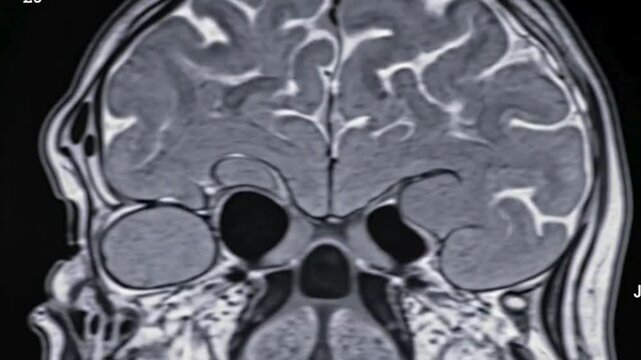

T2-weighted coronal plane fast spin echo MRI of the brain. Series description: Cor T2 FSE. Enlarged perivascular spaces are registered in the supratentorial white matter.

00:08